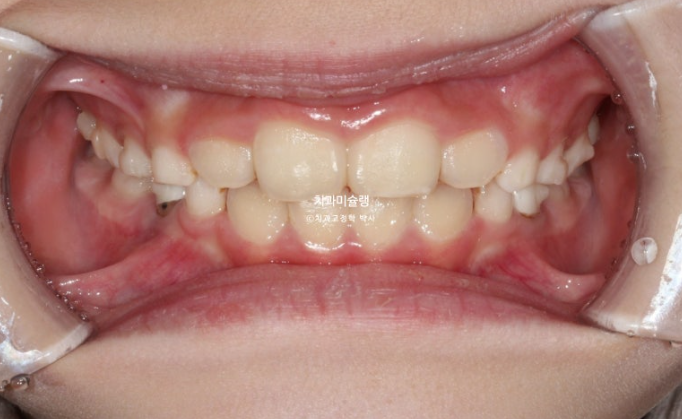

두번째 추가장치 16개를 모두 낀 후 치료를 종료했습니다.

25.08

유지장치는 과개교합 재발을 방지하기 위해 교합판이 들어간 유지장치를 잘때만 낍니다.

송곳니는 잘 올라오고 있습니다.

이제 전 후 비교 보겠습니다.

23.10~25.08